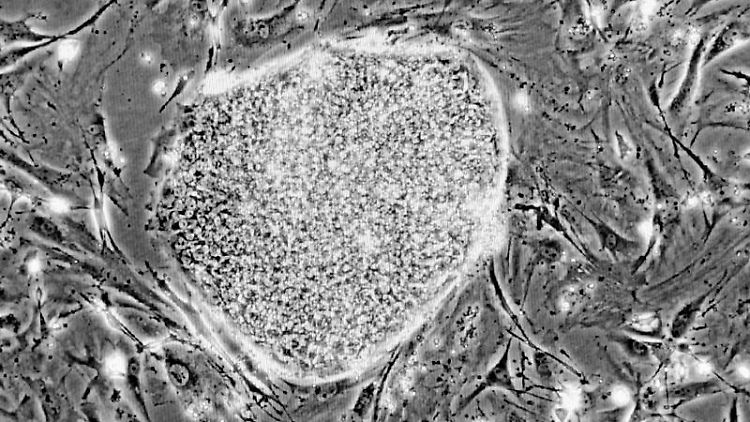

Zellen aus der Haut eines erwachsenen Menschen lassen sich in neue Blutaderzellen verwandeln. Dafür ist es noch nicht einmal nötig, das Ausgangsmaterial in den Status embryonaler Stammzellen zu versetzen. Dieses Verfahren lässt sich als "unvollständige Reprogrammierung" beschreiben und wurde nun erstmals zur Züchtung von Aderzellen benutzt.

Einem Team um Quingbo Xu vom King’s College London British Heart Foundation Centre ist es nun gelungen, die Hautzellen eines Erwachsenen zu Aderzellen umzuwandeln. Xu und Kollegen ließen die vier Signalproteine nur vier Tage lang auf menschlich Hautzellen wirken. Dies reichte aus, um die Zellen auf einen anderen Entwicklungspfad zu schicken. Das Team hat dafür auch einen Namen geprägt: PiPS (teilweise induzierte pluripotente Stammzellen). Dieses Verfahren verzichtet auf den vollständigen Stammzellen-Umweg. Nach den vier Tagen ließen die Wissenschaftler die Zellen in einer speziellen Nährlösung weiterwachsen. Mit der Zeit wurden daraus Zellen, die sich am Wachstum von Blutadern beteiligen.

Der Nachweis dafür gelang auf verschiedene Weise. Zunächst zeigte sich, dass die Behandlung das genetische Programm für Aderzellen startete. Im Tierversuch an Mäusen mit schweren Durchblutungsstörungen erhöhten die Zellen den Durchfluss. Zudem wurden die neuen Zellen im Labor in ein Gel gegeben, um deren Wachstum zu analysieren. Auch dort zeigten sie das typische Verhalten von Aderzellen, sie bildeten Röhren, in denen sie sich auch auf die richtige Weise anordneten.